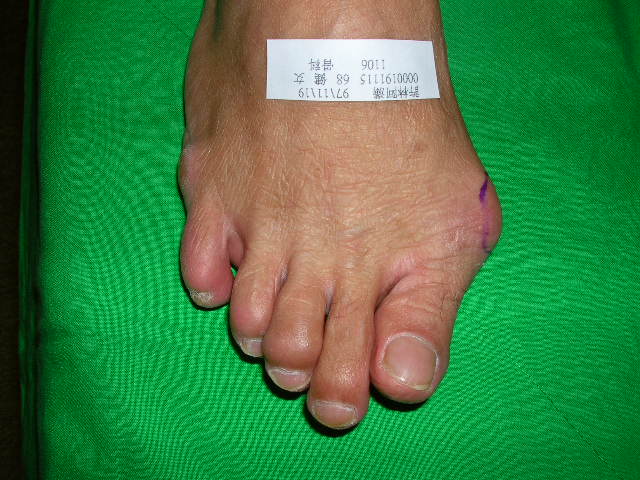

拇趾外翻是腳的一種先天變形。這種腳 大拇趾向鄰趾(第2趾)傾斜、拇趾 趾蹠關節像是轉個彎,使前腳呈三角形。拇趾外翻與遺傳有關,估計在30~50歲的一般人口中,約10% 的人如此,女性好發,比男性多4倍。傾斜的拇趾 會一天天越斜越厲害,壓迫、甚至頂起第2趾,造成關節變形,使腳不耐久站、走路;穿鞋(尤其是穿高根鞋) 困擾、疼痛,造成生活不便。(見圖1)

太緊的內收肌 肌腱,把大拇趾慢慢的向外拉,趾蹠關節也被拉成脫臼,產生關節滑液囊腫(即常稱的Bunion);或頂起鄰(第2)趾、或造成足底胼胝(雞眼),讓腳久站、走路、穿鞋疼痛。診斷上,除了看外觀外,還須照X-光,仔細評量趾-蹠交角、蹠-蹠交角的度數;趾-蹠關節 對位情形,及蹠底芝麻骨 (有2個) 脫位的程度……等,作為是否須手術治療的憑估。雖然,坊間有各式各樣的護具、矽膠墊、…..宣稱可復健矯正,但實際上沒有真正的效果,矯正還是要靠手術。